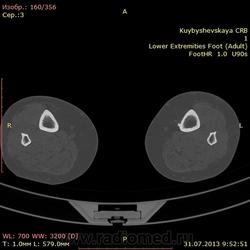

женщина. 69 лет. жалобы на боли в нижней трети голени слева в течении месяца. по снимкам врач написал периостит(к сожалению фотоаппарата нет под рукой)В ближайшее время травм не было. мне досталась только карточка. Пациента не видел. Помогите с диагностикой. вроде бы на зло не похоже. или ошибаюсь?

На зло непохоже, нет мягкоткотканного компонета. Передне-медиальная поверхность голени - самое место для травмы. Только термин "периостит" мне тоже не нравится, написал бы - локальное обызвествления мягких тканей, вероятнее всего посттравматического характера.

По снимкам описал бы как обызвествившуюся гематому, а по КТ больше тянет на экзостоз, только основание очень широкое.